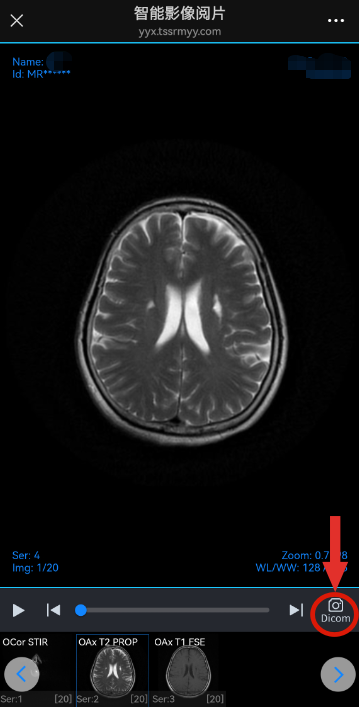

STEP1 扫描纸质报告单右上角二维码 STEP2 扫描登记小票上方二维码 STEP3 为了保护患者隐私,保证信息安全。 扫描二维码之后需要输入手机号后4位或者身份证号码后6位进行身份验证。验证成功之后才能看到本次检查结果的原始报告和影像文件。 STEP4 点击“报告单”,可查看本次检查的原始报告单。 STEP5 点击“查看影像”,可查看本次检查的原始影像(DICOM格式)。该影像可实现放大、缩小、旋转等功能。